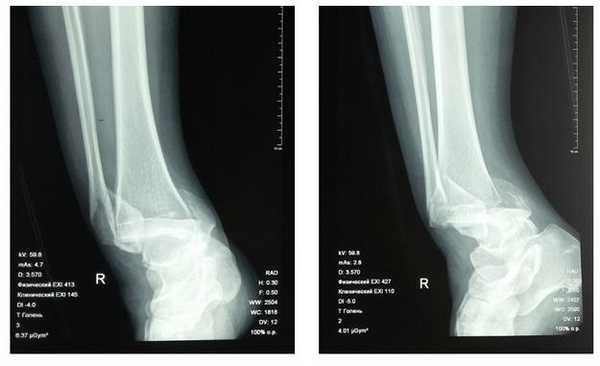

Пациентка Т. 80 лет. Травма за 3 недели до обращения, получила перелом обеих лодыжек правой голени со смещением, подвывихом стопы кнаружи. Обратилась в РТП, выполнена рентгенография, наложена гипсовая повязка. В связи с сохраняющимся выраженным отёком и болевым синдромом обратилась в клинику К+31.

На рентгенограммах в гипсе определяется значительный подвывих таранной кости кнаружи, консолидирующийся перелом нижней трети малоберцовой кости.

В день обращения пациентка послоностью обследована, проведено оперативное лечение, открытая репозиция, остеосинтез перелома нижней трети малоберцовой кости пластиной, внутренней лодыжки винтом, внутренняя лодыжка дополнительно фиксирована анкерным фиксатором.

На контрольных рентгенограммах после операции положение отломков, металлофиксаторов правильное, подвывих таранной кости устранён.

Пациентка выписана на 2 сутки после операции на амбулаторное долечивание.

Пациентка Л. 50 лет, травма в быту, получила закрытый перелом обеих лодыжек с вывихом стопы кнаружи и кзади. Данный случай интересен значительным повреждением мягких тканей произошедшем при травме и потребовавшем значительных усилий в борьбе с отёком, а также морфологией перелома внутренней лодыжки, сломавшейся одним большим блоком вместе с задним краев большеберцовой кости, что потребовало её фиксации при помощи пластины и винтов.

В связи с выраженным отёком мягких тканей, высоким риском некроза краёв ран и инфекционных осложнений пациентке с целью предоперационной подготовки выполнялись скелетное вытяжение, сосудистая и метаболическая терапия, лимфодренаж, физиотерапия. После спадения отёка, на 3 день после поступления выполнено оперативное вмешательство: открытая репозиция, остеосинтез переломов наружной и внутренней лодыжек пластинами и винтами.

Через 4 дня пациентка выписана на амбулаторное долечивание. Послеоперационные раны зажили первичным натяжением, швы удалены через 14 дней.

Через 6 недель после первичного вмешательства произведено удаление позиционного винта, пациентка приступила к активной разработке движений в голеностопном суставе.

Амплитуда движений через 8 недель после травмы и оперативного вмешательства по поводу этого тяжёлого повреждения близка к полной. Пациентка ходит с полной опорой, не используя костыли или трость, не хромает, боли не беспокоят. Сохраняется умеренный отёк в области голеностопного сустава.